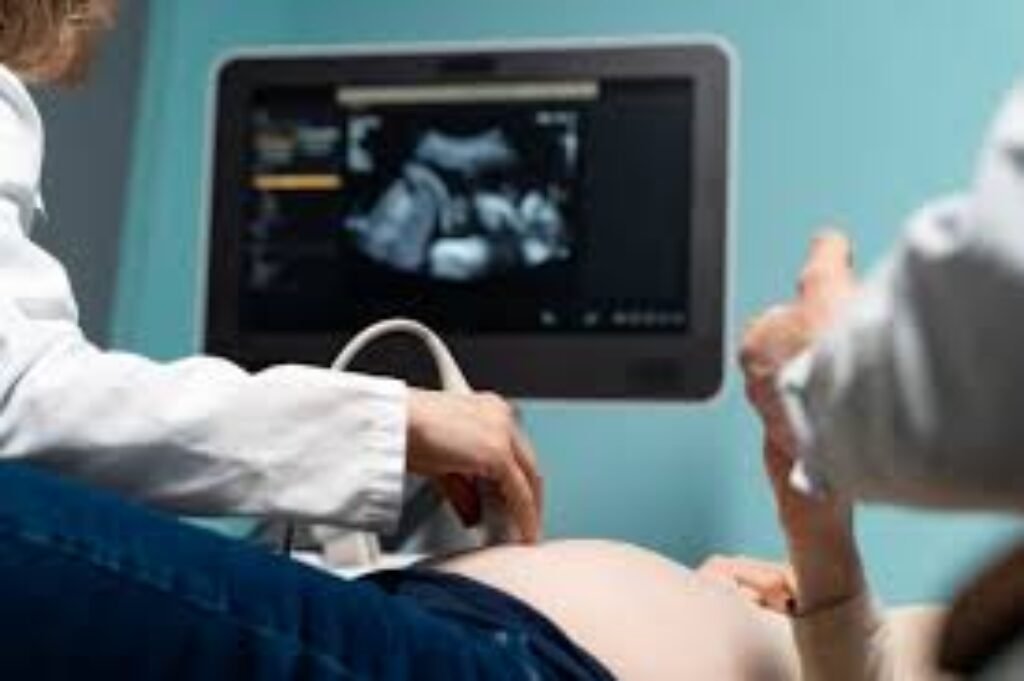

A pregnancy ultrasound uses safe sound waves to confirm the pregnancy, check the baby’s development, and assess your overall reproductive health. While every pregnancy is unique, certain stages offer the most reliable information.

- 6–8 weeks: Confirms pregnancy, location (important for ruling out ectopic), number of babies, and early heartbeat